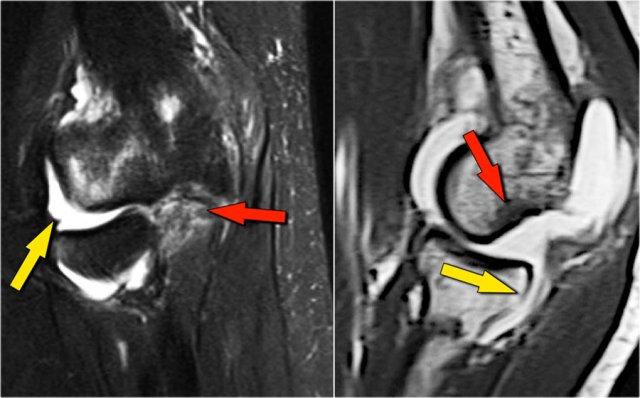

Here a lateral view of the elbow of a patient who fell on the outstretched arm.

The radiograph shows joint effusion (red arrows) and a coronoid fracture (yellow arrow).

Continue with the MR-images.

Now here is the MR.

Study the images and then continue reading...

Coronal view:

1. Lateral collateral ligament is completely stripped (yellow arrow).

2. radial head is subluxed.

3. marrow edema of the coronoid process due to the fracture (red arrow).

Sagittal view:

1. Radial head is a little bit subluxed posteriorly (yellow arrow).

2. Large effusion and capsular disruption posteriorly.

3. Contusion of the posterior side of the capitellum as a result of impaction by the coronoid process (red arrow).

All these signs are the result of a posterior dislocation.